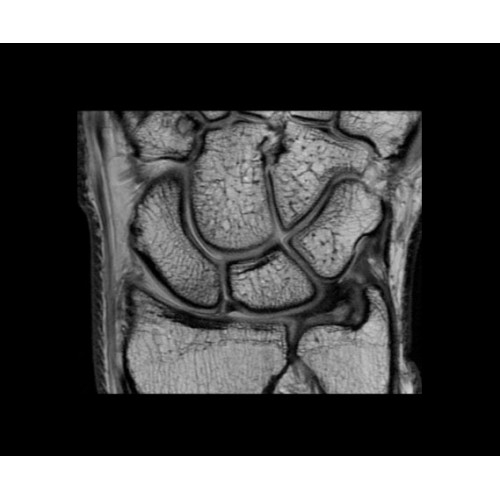

• МРТ с функцией нулевого времени эхо (ZTE) отличается точностью, возможностью персональных настроек и отсутствием ионизирующего излучения. Она приходит на смену традиционному исследованию на основе рентгеновского излучения. МРТ с функцией нулевого времени эхо (ZTE) на базе SIGNA ПЭТ/МРТ является более надежной и быстрой по сравнению с системами, использующими сверхмалое время эхо (UTE).

• Специальный пакет приложений для измерения и сравнения объемных изображений ЦНС с нормами поможет вам в диагностике нейродегенеративных заболеваний, а дополнительные инструменты визуализации — в постановке точного диагноза с помощью бета-амилоидов и радиоизотопных маркеров ФДГ.